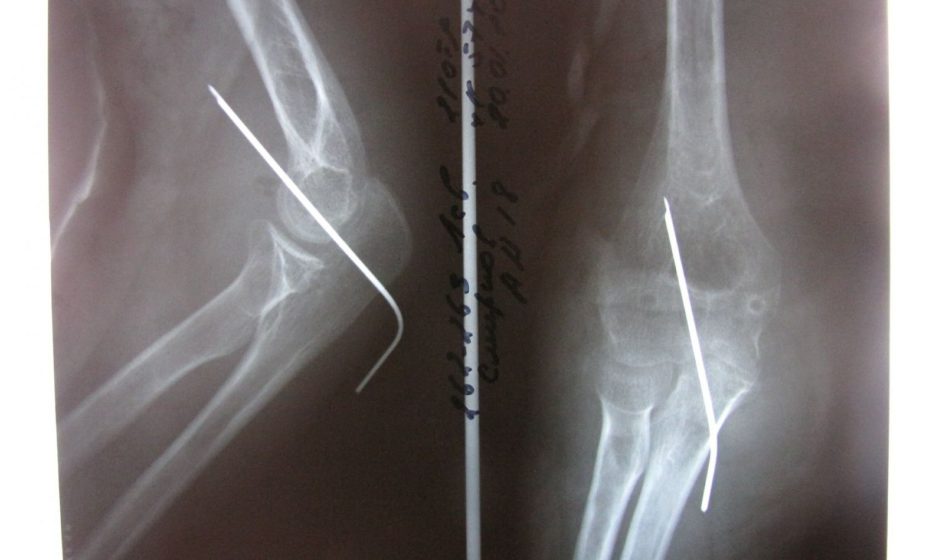

Диагноз «перелом руки» был поставлен по рентгеновскому снимку, отправленному медсестрой с помощью мессенджера WhatsApp

В мае в приемный покой Намской центральной районной больницы с признаками перелома руки поступил ребенок 2005 года рождения. Медсестра вызвала дежурного врача-хирурга. Однако врач на осмотр пациента не явился, а диагноз «перелом руки» поставил по рентгеновскому снимку, отправленному медсестрой на его телефон с помощью мессенджера WhatsApp.

Как утверждали в больнице, находясь в пути, хирург поручил рентгенологу сделать ребенку снимок, и попросил перезвонить ему, когда тот будет готов. Снимок был передан на электронную почту, консультация проведена в рамках телеконсультирования, сообщает ИА Regnum. Определив по снимку, что перелом без смещения, врач получил медсестре наложить гипс и пригласить пациента в понедельник на повторный осмотр.